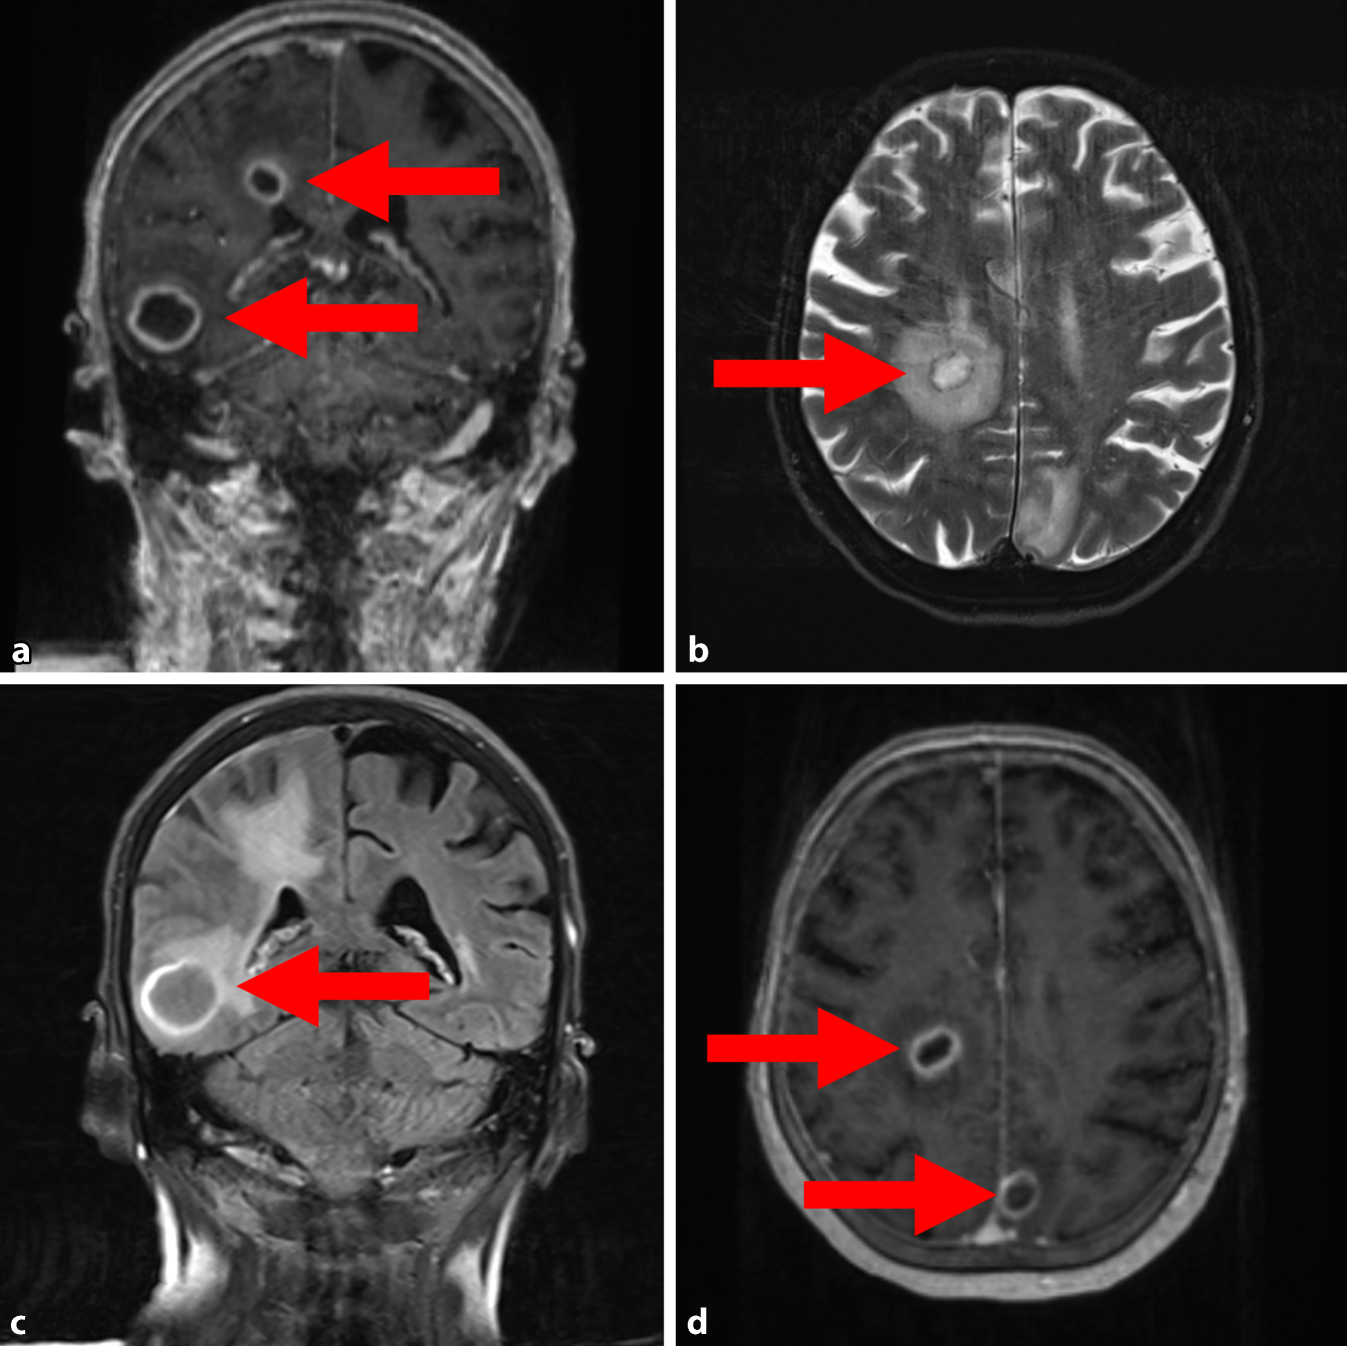

Abb. 3

Multiple intrakranielle Abszesse (Pfeile) in der cMRT, die durch paradox-septische Embolien entstanden sind, jeweils markiert durch Pfeile. a Post-KM MP-RAGE koronar. b T2 TSE FS axial. c FLAIR koronar. d Post-KM MP-RAGE axial

Zur weiteren Diagnostik wurde bei im Verlauf neu aufgetretenen klinischen Hirndruckzeichen (Kopfschmerzen, Übelkeit/Erbrechen) eine zerebrale Computer- und Magnetresonanztomographie (cCT/cMRT) durchgeführt. Es zeigten sich mindestens acht kontrastmittelaufnehmende, intraaxiale Läsionen (Abb. 3), die radiologisch primär als Abszessformationen interpretiert wurden.

Es lag eine Blutstrominfektion mit S. anginosus vor, welche durch den iatrogenen Lymphknotenabszess nach EBUS-gestützter Lymphknotenbiopsie mit Fistelung in die VCS entstand. Sekundär kam es über einen ASD zu paradox-septischen Embolien mit multiplen Hirnabszessen.